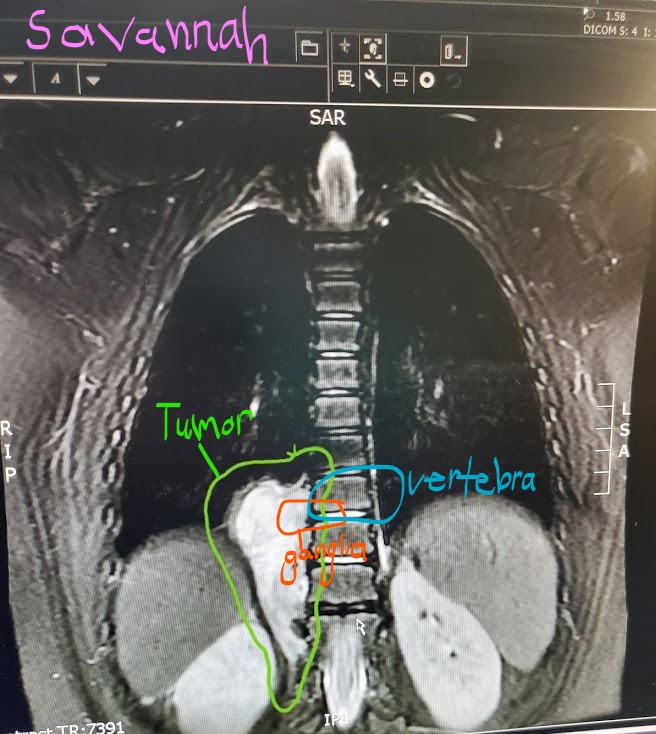

- The images below help you visualize where in Savannah’s body this tumor grew. The cells grew and multiplied into a mass that grew into her abdominal and thoracic cavity pushing against her right kidney, adrenals and diaphragm. Once it had grown that direction it started to push it’s way into the vertebra. It did NOT originate from the spine itself, but from the ganglia outside of the vertebra.